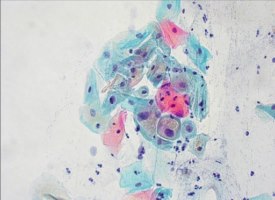

Il Pap test é in grado di rilevare la presenza dell'HPV poichè le cellule infettate da questo virus assumono un aspetto particolare, diventano cioè “coilociti”, cellule con nucleo più grande, più scuro e circondato da un alone bianco. La presenza di coilociti pone diagnosi di infezione da HPV.

Alcuni microrganismi provocano modificazioni cellulari tipiche, le quali permettono di rivelare la loro presenza. Le cellule infettate dall'HPV per esempio assumono un aspetto particolare, diventano cioè “coilociti”, cellule con nucleo più grande, più scuro e circondato da un alone bianco. La presenza di queste cellule coilocitiche pone diagnosi di infezione da HPV. Altri microrganismi che provocano alterazioni cellulari specifiche rilevabili col Pap Test sono: Trichomonas vaginalis, Candida, microrganismi tipici di una vaginosi batterica, Actinomiceti, Herpes simplex virus. - ANORMALITÀ DELLE CELLULE EPITELIALI